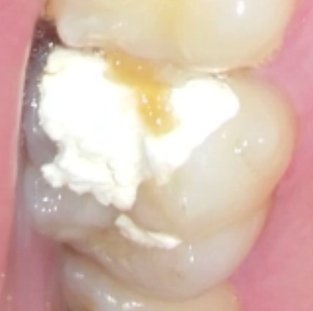

Обращаюсь к Вам со следующим вопросом: примерно месяц назад, появились ноющие боли в верхней шестерке слева (зуб побаливал и раньше, но у меня на тот момент, было другое серьезное заболевание в организме и не было времени лечить зуб). Две недели назад, я все-таки пошла к стоматологу, она посмотрела, сказала, что зуб сложный, так как дырка между зубами, под уколом почистила каналы и поставила временную пломбу, сказала, что если после того, как отойдет укол будет болеть, прийти к ней. Спустя два часа появилась сильная боль, я опять пошла к стоматологу, она поставила мне мышьяк на два дня, но на следующее утро, я проснулась и заметила, что припухла десна, вновь пошла к врачу, она сказала, что немного мышьяка попала на десну, все переделала и оставила еще на сутки. На следующем приеме она поставила мне временную пломбу с лекарством на неделю, два дня я ходила, ничего не беспокоило, на третий день я заметила небольшую припухлость возле десны, пошла к врачу, но она не работала, меня осмотрел ее коллега и сказала срочно удалять зуб, так как по нему было больно стучать. Повела меня к хирургу, он все осмотрел, потрогал и сказал, что удаление не требуется, велел открыть зуб и полоскать содой и назначил принимать Доксициклин 5 дней, а в понедельник сказал прийти к своему врачу. Я все так и сделала, после открытия зуба, по нему все равно было больновато стучать. На слудеющем приеме мне сделали снимок, ничего страшного там не увидели, мой врач еще раз почистила каналы, без укола, было больновато, в одном месте даже сильно больно, обработала их каким-то средством и поставила лекарство (очень горькое), сказала, что положила побольше ваты, что все должно быть хорошо. Действительно, мне стало лучше, зуб почти сразу же стих, даже стучать по нему было не больно, проходила с этим лекарством пять дней и вот вчера доктор вытащила эту временную пломбу, еще раз почистила каналы, было уже не так сильно больно, и сказала, что теперь нужно поставить лекарство без ваты, напрямую в каналы, предубредила, что будет больно, с помощью машинки она поставила какое-то желтое лекарство вглубь каналов, боль появилась сразу, но доктор предупредила, что это норма. После приема, я сразу же выпила таблетку Нурофена и боль стихла, больше такой сильной боли не было. Но сейчас меня беспокоит то, что мне опять больно постукивать по зубу (с боку), он немного еще понывает переодически и как будто чешется иногда.

Уважаемая пациентка! Судя по Вашему рассказу и методах лечения, у Вас обострение хронического периодонтита. Методы лечения правильные и боль при установке лекарства (Метапекс) также норма. Единственное, что в верхних шестых зубах в 90% бывает дополнительный четвертый канал и его необходимо найти и пролечить, причина воспаления скорее всего именно в нем.